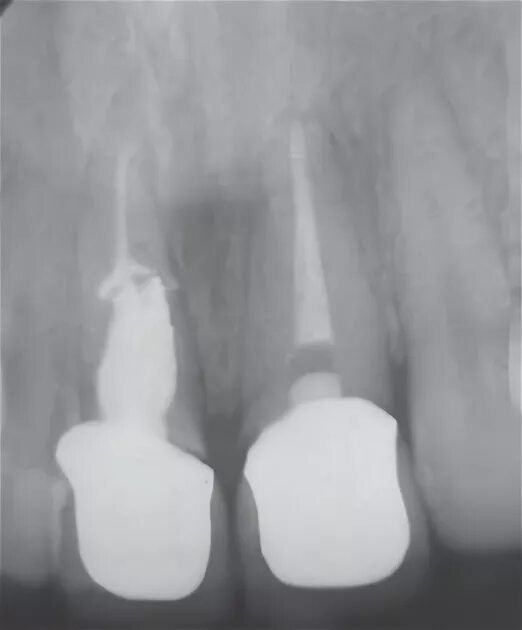

Признаки резорбции